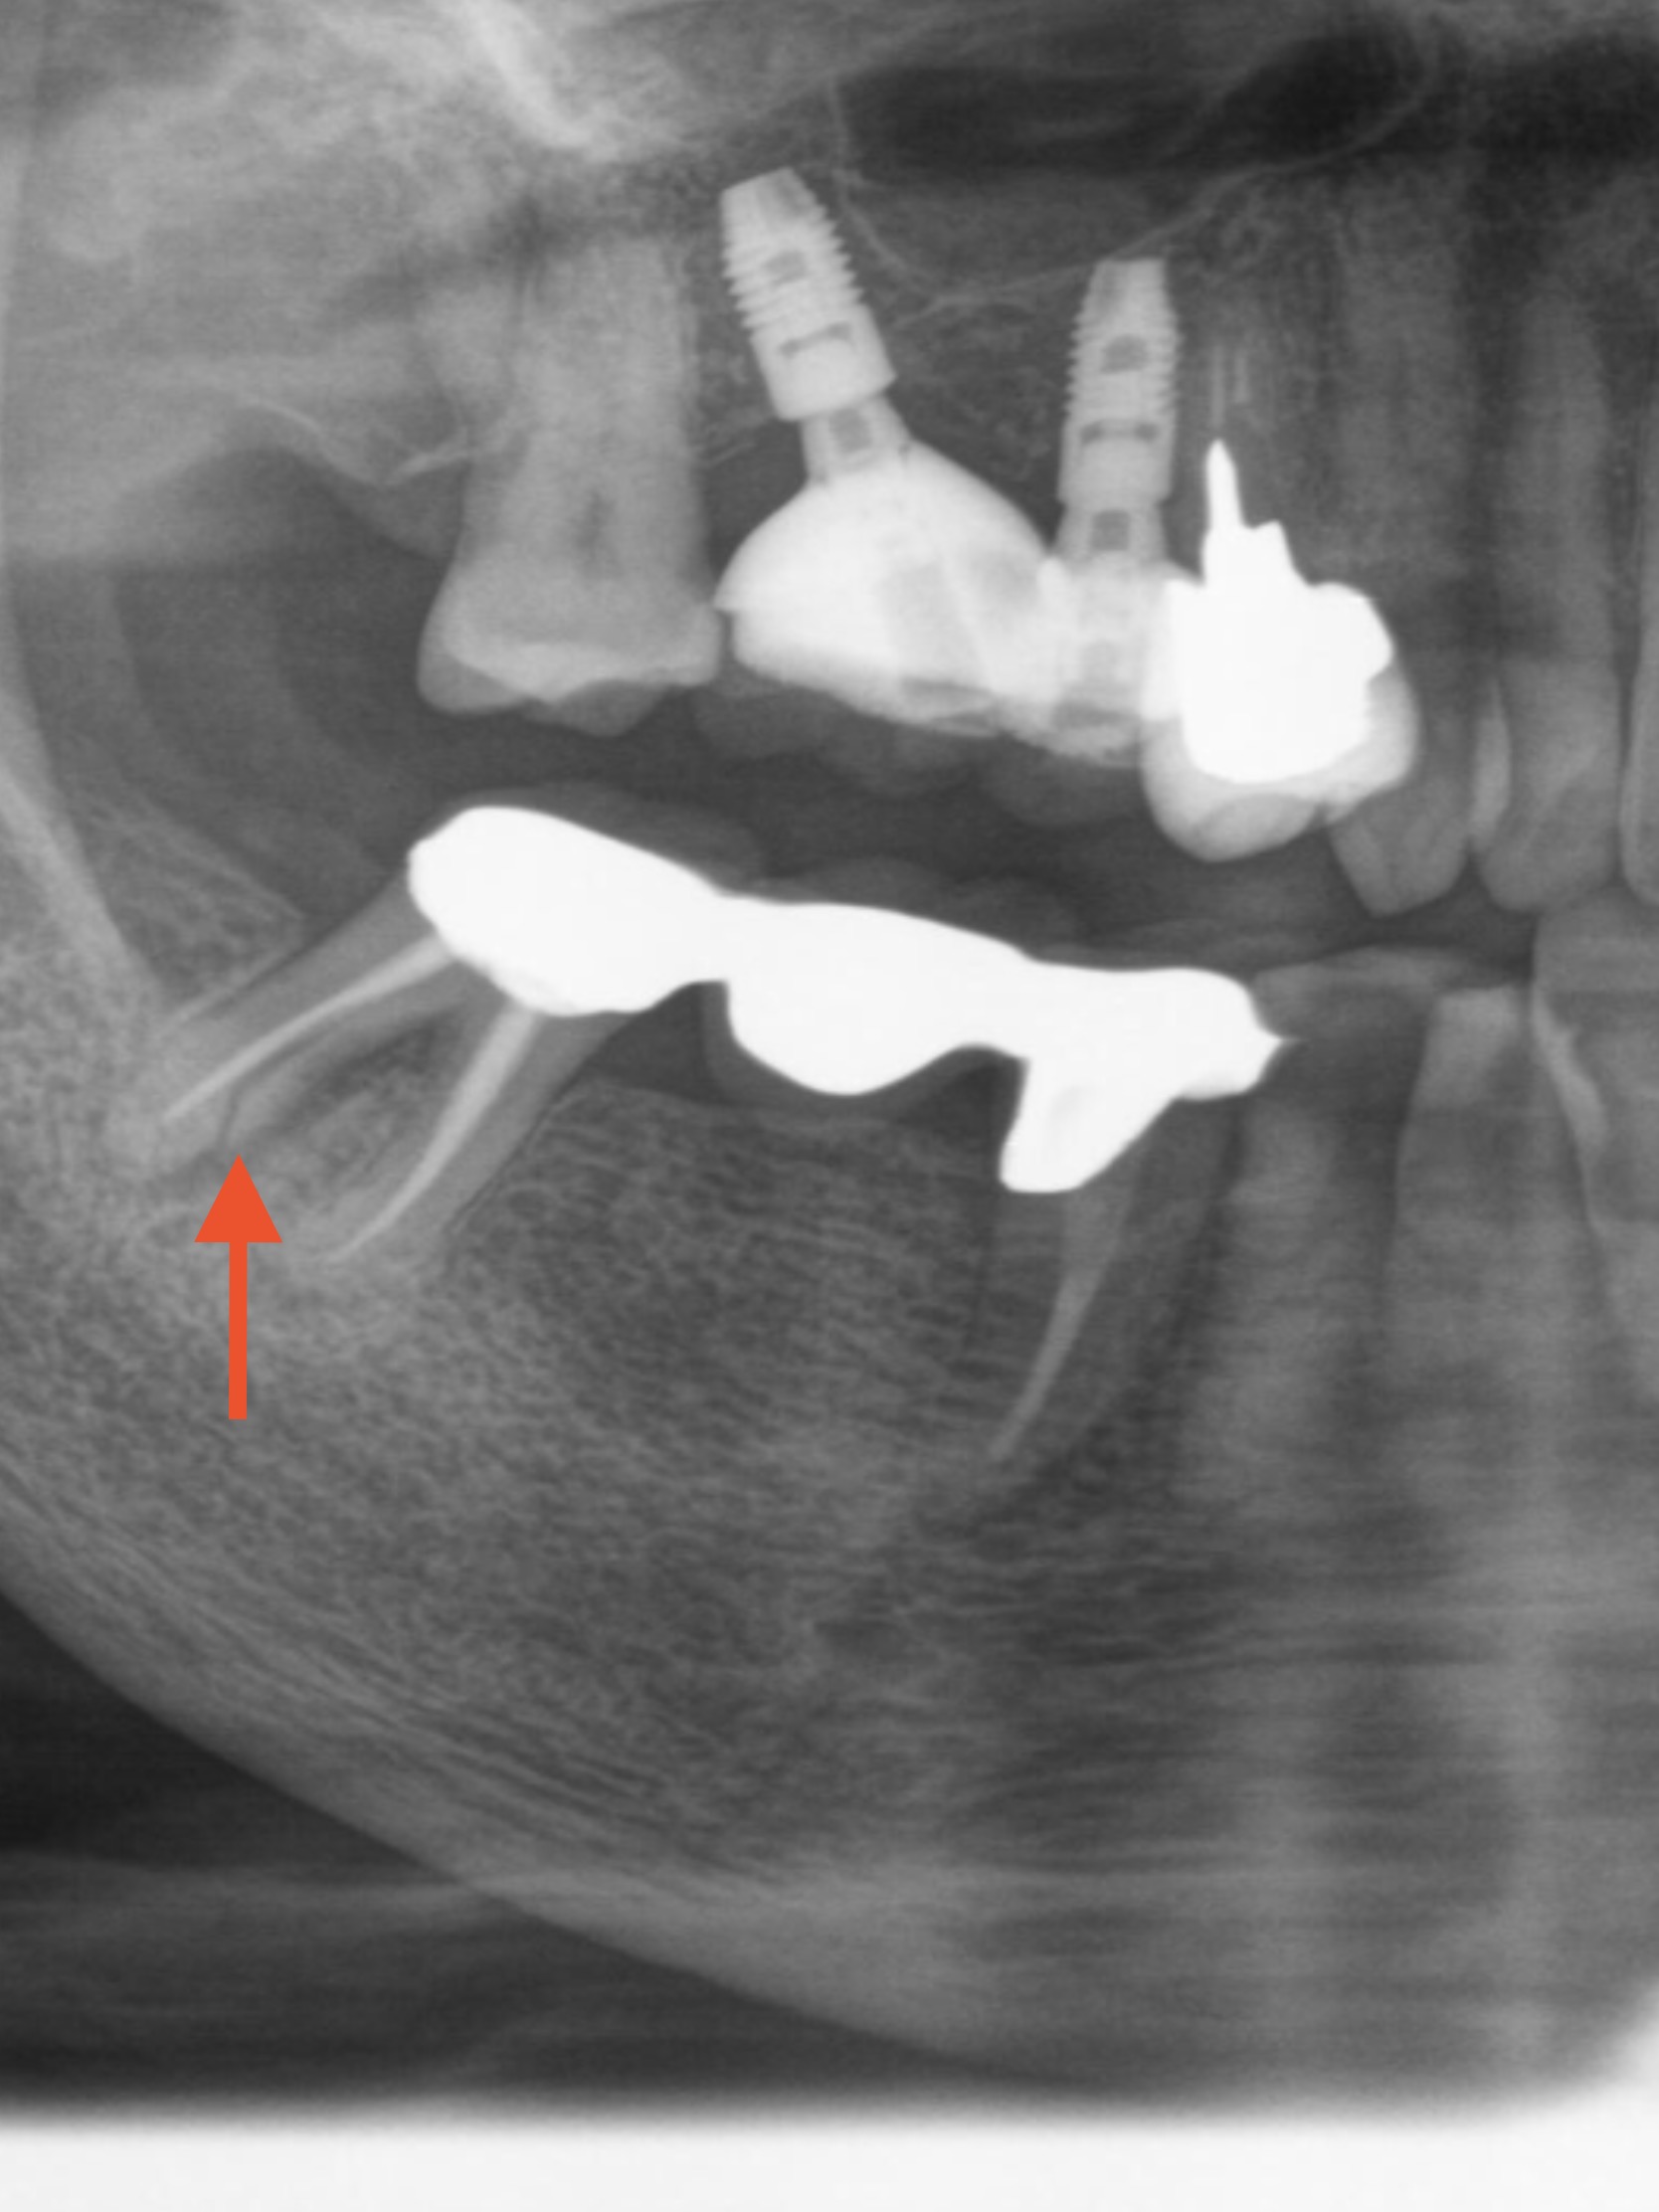

レントゲンを撮り、歯周ポケットの検査などを行い

右下の一番奥、ブリッジの支えの歯が割れている(写真赤矢印部)のが

原因だと分かりました。